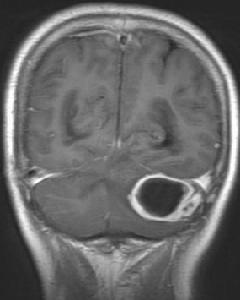

腦膿腫MRI顯示隨病因而異。耳源性腦膿腫的細菌主要入侵途徑是經鄰近的骨結構(如鼓室蓋)直接蔓延至硬腦膜、蛛網膜、血管、血管周圍間隙,從而進入顳葉腦實質,形成膿腫(圖55-1),也可經鼓室蓋後壁或Trautman三角(上方為岩上竇、下方為面神經管、後方為乙狀竇)引起小腦膿腫。在少數病例,並有血栓性靜脈炎時,感染性栓子可經靜脈竇逆行或經導靜脈(或動脈)傳入腦,引起遠隔部位如頂、枕、額葉、小腦蚓部或原發病灶對側的腦膿腫。鼻源性腦膿腫的感染是細菌經額或篩竇壁,侵犯硬腦膜形成硬腦膜外(或下)膿腫,進而炎症擴散入腦實質和血管(特別是靜脈),形成腦膿腫。血源性腦膿腫細菌侵入腦實質的途徑有:①經動脈血循環,多見於膿毒血症和胸腔內感染及細菌性心內膜炎,細菌或感染性栓子經動脈血循環到達腦內,先天性心臟病因有動靜脈短路,大量靜脈血不經肺過濾,直接進入左心,使細菌或感染栓子直達腦內。青紫型心臟病者常伴有紅細胞增多症,血粘度增加,易形成栓子和造成腦栓塞,腦組織缺血缺氧、壞死,更有利細菌繁殖而形成腦膿腫;②經靜脈血循環,見於頭面部感染、顱骨骨髓炎、牙周膿腫等,細菌可經面靜脈與顱內的吻合支或板障靜脈、導靜脈等侵入顱內;③經椎管內靜脈叢,肝、膽、膈下膿腫、泌尿系感染和盆腔感染,可經脊柱周圍靜脈叢與椎管內之靜脈吻合進入椎管內靜脈,再經椎靜脈逆行入顱內。損傷性腦膿腫因硬腦膜破損,異物侵入顱內將細菌帶入。

小腦腦膿腫MRI顯示1、頭顱X線平片 可發現乳突、副鼻竇和顳骨岩部炎性病變、金屬異物、外傷性氣顱、顱內壓增高和鈣化松果腺側移等。

小腦腦膿腫MRI顯示1、化膿性腦膜炎:有高熱、脈快,腦膜刺激征明顯,但無局限神經定位征,腦脊液白細胞和蛋白質增高,腦超聲檢查,腦血管造影和CT掃描均正常。